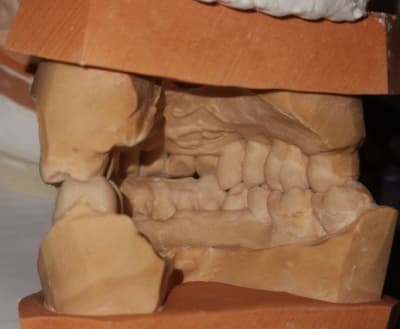

modèles de départ, photos avec le téléphone, désolé, mais ça donne une petite idée

--